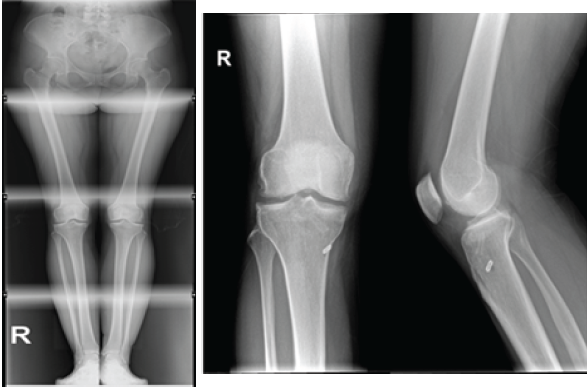

Due to the refractory pain and persistent difficulty in performing daily activities 1 year later, a weight-bearing full-leg X-ray was performed (Fig. 1) and showed a neutral aligned knee with a hip-knee-ankle angle of 1° varus and normal values for the lateral distal femoral angle and the medial proximal tibial angle. Operative treatment with lateral meniscus autograft transplantation using a hamstring tendon was proposed.

Figure 1: Full-leg X-ray.